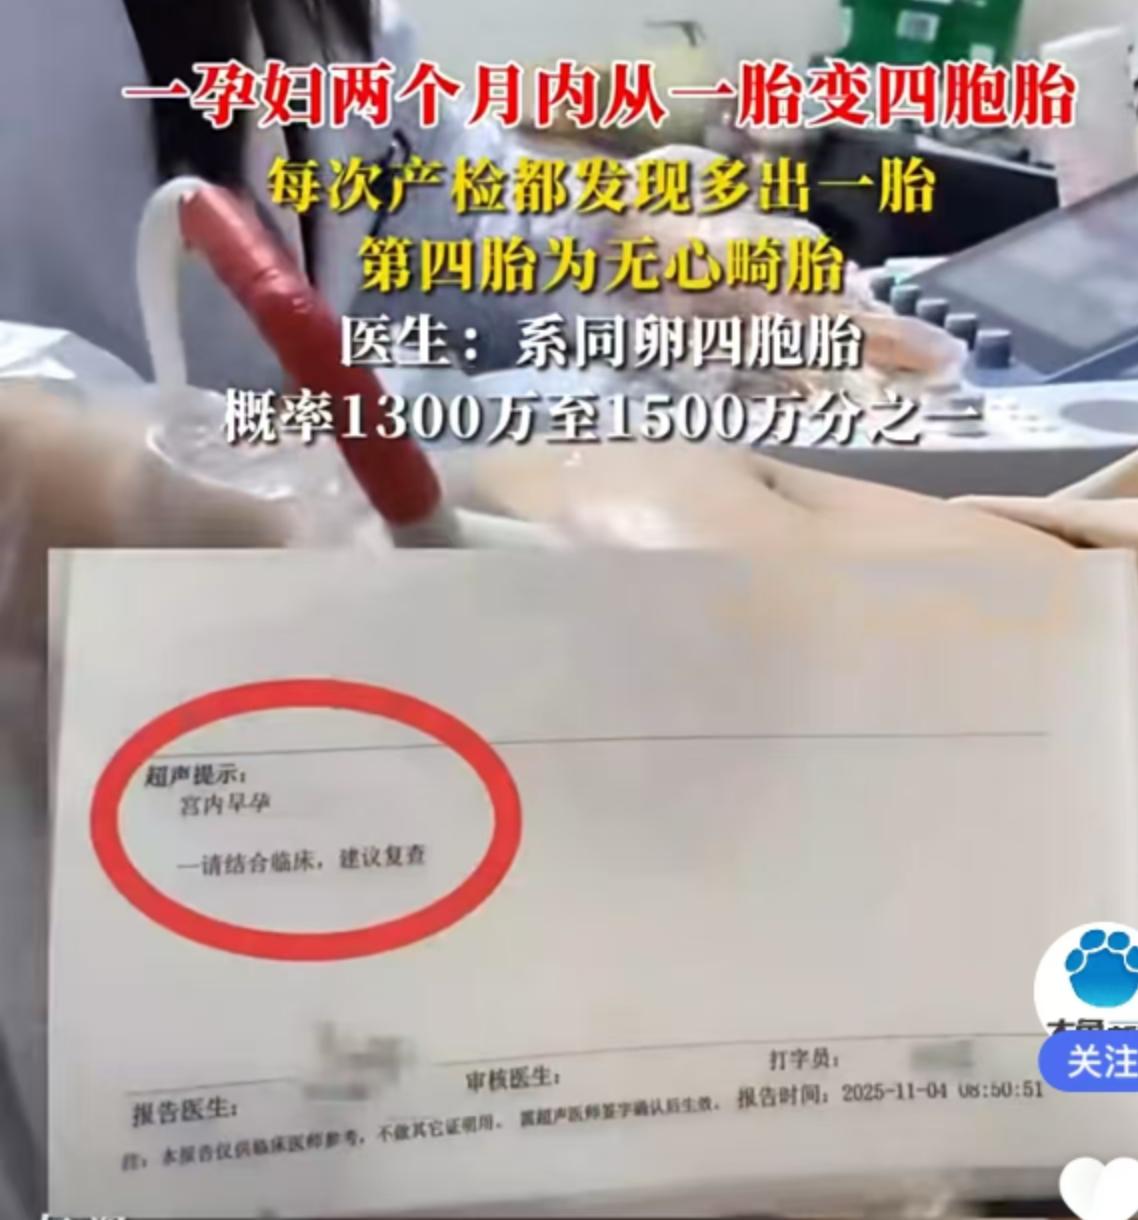

辽宁抚顺的一位准妈妈最近经历了人生中过山车般的时刻。怀孕16周的王女士,原本只是按部就班地进行产检,却在医院拿到了一份极其罕见的诊断报告。从去年11月到12月,短短一个月的时间里,她在医院进行了四次产检,每一次彩超单上的图像都在发生变化——最终确认,她怀上了四胞胎。 这并非普通的四胞胎。根据相关医生的诊断,王女士怀上的是同卵四胞胎。在医学领域,同卵四胞胎的发生率极低,属于非常罕见的个案。更复杂的情况在于,医生指出第四个胎儿为“无心畸胎”。这是一个专业性很强的术语,意味着这个胎儿虽然没有正常的心脏发育,但依然依赖其他胎儿的血液循环在母体内生存。这种特殊的医学状况,无疑给整个孕期增添了巨大的不确定性和风险。 对于普通家庭而言,多胞胎往往意味着双倍的喜悦,但在医学视角下,这更多代表着高风险妊娠。从数据来看,自然受孕情况下同卵四胞胎本就凤毛麟角,而伴随无心畸胎的情况更是让保胎之路布满荆棘。王女士在抚顺当地医院进行的这四次检查,实际上是一个不断排查和确认的过程。每一次彩超,不仅是在数胎儿的数量,更是在评估母体和每一个胎儿的生存质量。 网友们对此议论纷纷,有人感叹生命的奇妙与不易,也有人为即将到来的抚养压力感到担忧。毕竟,四个孩子的降生,对家庭的经济状况、父母的精力都是极大的考验。目前摆在王女士和家人面前的,不仅是喜悦,还有如何根据医生的专业建议,制定最科学、最安全的后续妊娠方案。 这起事件也给广大备孕及孕期女性提了个醒:规范的产检流程至关重要。像王女士这样,通过连续、定期的超声检查,才能及时发现多胎妊娠及胎儿发育异常等特殊情况。面对罕见病例,医学干预和监测是保障母婴安全的最有效手段。祝愿这位准妈妈能平安度过接下来的孕期,也希望这个小生命群体能在现代医学的保驾护航下,迎来最好的结局。 以上内容仅供参考和借鉴